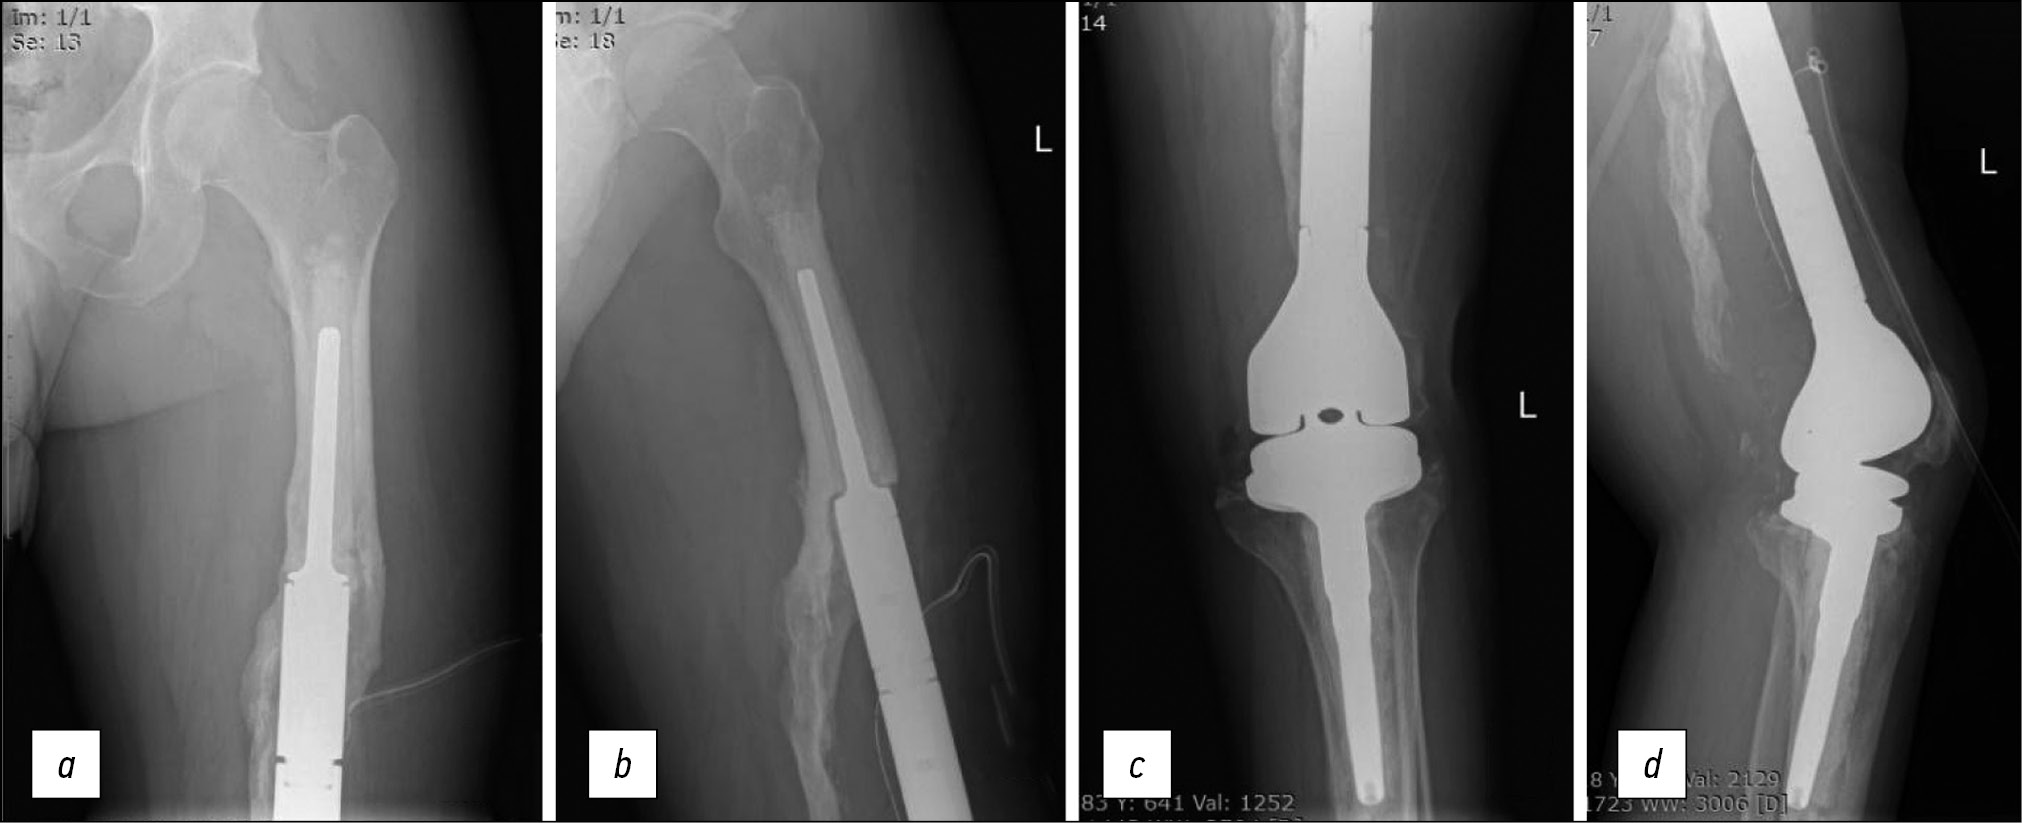

On February 14, 2019, the left knee joint endoprosthesis was removed, with replacement of the defect with an articulating spacer (Fig. 7).

Fig. 7. Manufacturing stages of articulating 3D spacer: a — creating a mold for manufacturing a 3D spacer; b, c — fabricated articulatory 3D spacer of the knee joint; d — defect replacement after removal of the knee endoprosthesis with an articulatory 3D spacer.

Considering the presence of concomitant chronic disease with skin lesions (psoriasis), recurrent episodes of implant infection with an identical bacterial pathogen, and similar bacteriogram, the interval between the stages of two-stage re-endoprosthesis was increased to 1 year. To preserve the functional potential and restore quality of life, a customized articulating spacer was used to replace the defect after the removal of the left knee joint endoprosthesis. This design made it possible to maintain the flexion angle of the knee joint up to 80° and provide full load on the left lower extremity 3 months after surgery, which made it possible to abandon crutches and switch to using a cane (Fig. 8).